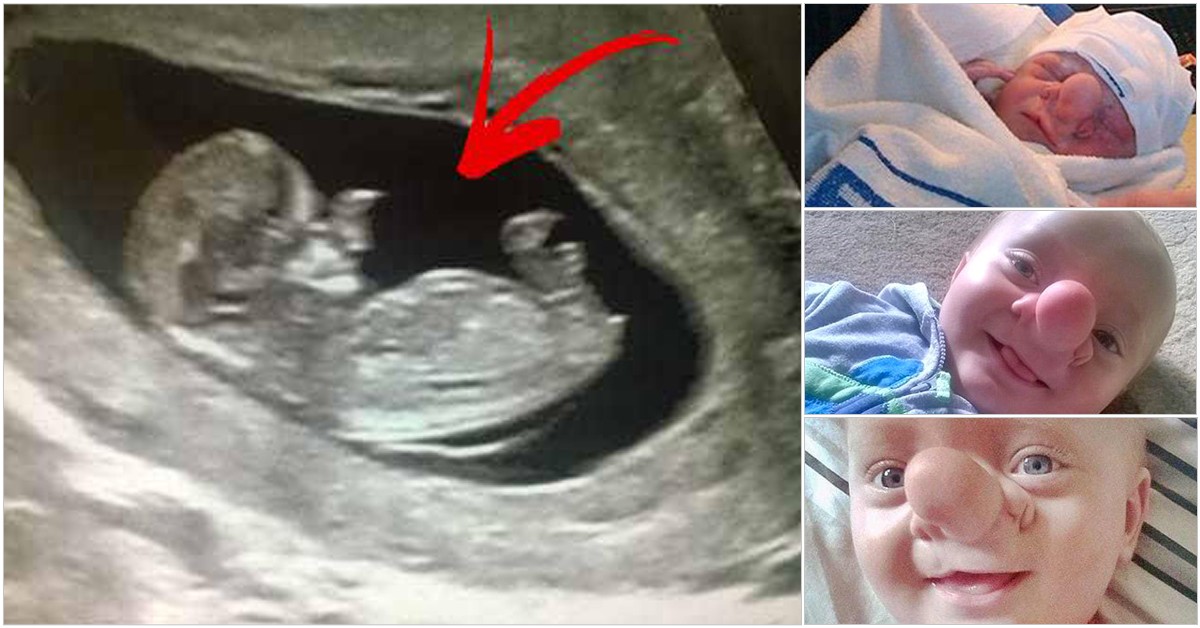

Amy poole, ikinci bebeğine hamileydi. ancak bu sıradan bir hamilelik değildi. doktora gidip ultrasona girdiğinde, hayatının şokunu yaşadı. doktor, 20 haftalık bebeğim yüzünde hiçte normal olmayan bir şeyler görmüştü.

Amy, çocuğundan yine de vazgeçmedi ve onu dünyaya getirdi 'onu kucağıma ilk aldığımda açıklaması zor, büyük bir şok yaşadım'

Bebeğine ollie ismini veren amy için, çocuğunun ilginç görüntüsü yüzünden hayatları pekte kolay geçmedi.

Minik ollie 'sefalosel' hastası. sefalosel ya da beyin fıtığı; beyin dokusunun kafa tasındaki bir açıklıktan dışarıya çıkmasıdır. anne rahmindeki gelişim süreci boyunca kafanın arkasındaki ya da önündeki bir açıklık sonucu bu durum gerçekleşebilir.

Amy, çocuğuna garip bir şekilde bakılmasının, ona çirkin denmesinin kendisini çok üzdüğünü ancak sevgisinin asla değişmeyeceğini şu sözlerle anlatıyor 'ollie bence mükemmel bir çocuk. o benim minik pinokyom ve onunla bundan fazla gurur duyamazdım.'

Ollie'nin bir de ablası var; annabelle. ollie ablasından farklı olduğu için onu kıskanıyormuş. ollie ile dalga geçenlerinde yanı sıra iyi kalpli insanlarda var. ollie ve ailesinin bu durumuna üzülen bazı yardımseverler bağışlarda bulundular ve ollie bir takım estetik operasyonlar geçirdi.

Geçirdiği estetik operasyonlar sonrası burnundaki çıkıntıdan kurtulan ollie kısmen de olsa iyileşti.